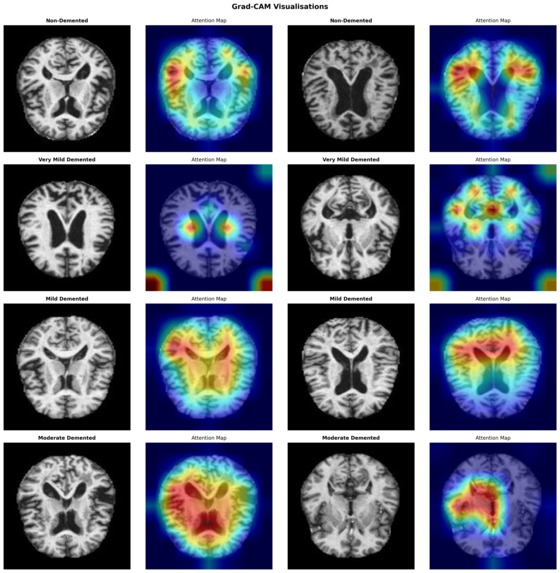

A key focus was ensuring the system produces meaningful probability estimates rather than overconfident predictions. Post-hoc temperature scaling was applied to improve probabilistic calibration, and Grad-CAM visualisations were used to verify that the model attends to anatomically plausible brain regions associated with Alzheimer’s pathology.